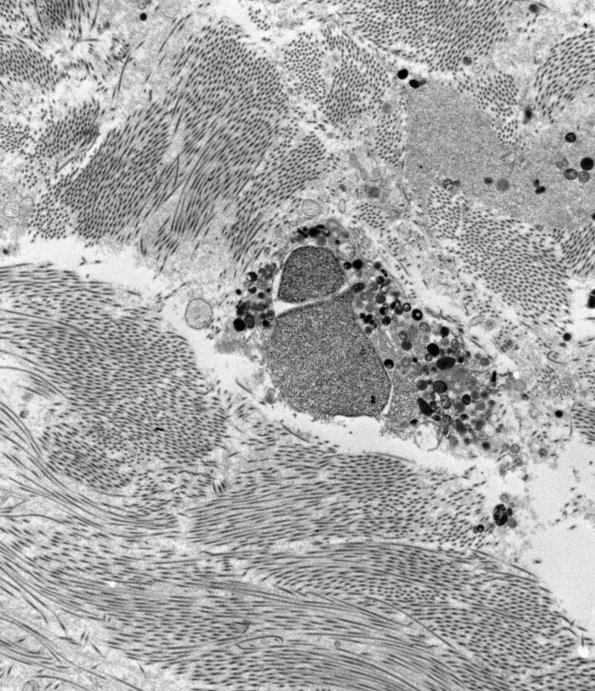

12E1-6 Within collagenous areas swollen structures were encountered which consist of autophagic vacuoles and tubulovesicular elements. We think these are swollen regenerative structures similar to axonal growth cones, likely by deviation into an area not conducive to regeneration. (electron micrographs)